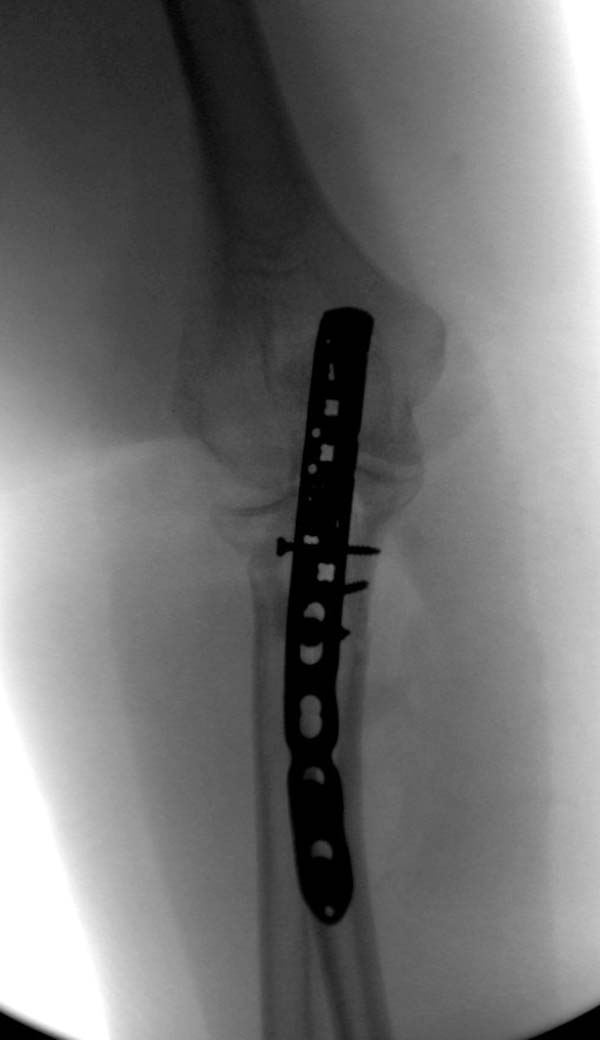

Здесь представлены несколько случаев и как видно больше больных с

серьезными повреждениями, чем изолированные..

В первом случае перелом Монтеджи, где доперационно сделано оценка

положения головки к остальным элементам под рентгеном. Учитывая

правильность взаимотношении произведена фиксация только локтевого

отростка, Второй случай, заменена на протез, и третий, кроме фиксации

головки - реконструкция capitellum латерального мыщелка.

Имя     : 1 Radial head olecranon.jpg

Тип     : image/jpeg

Размер  : 22714 байтов

Описание: отсутствует

Url     : http://weborto.net:8080/pipermail/ortho/attachments/20131119/c3543de4/attachment-0008.jpg